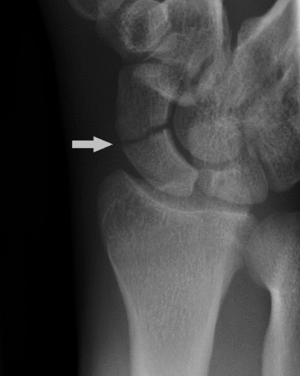

A subtle scaphoid fracture